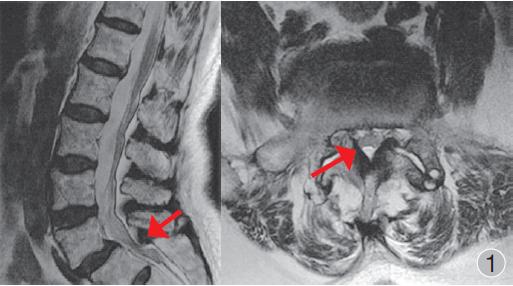

2、腰椎管狭窄有许多类型,比如合并脊柱侧弯、脊椎滑脱等。

4、退行性脊椎滑脱是由于长期的椎间盘导致的椎间关节不稳定,表现为上位脊椎向前发生滑移。